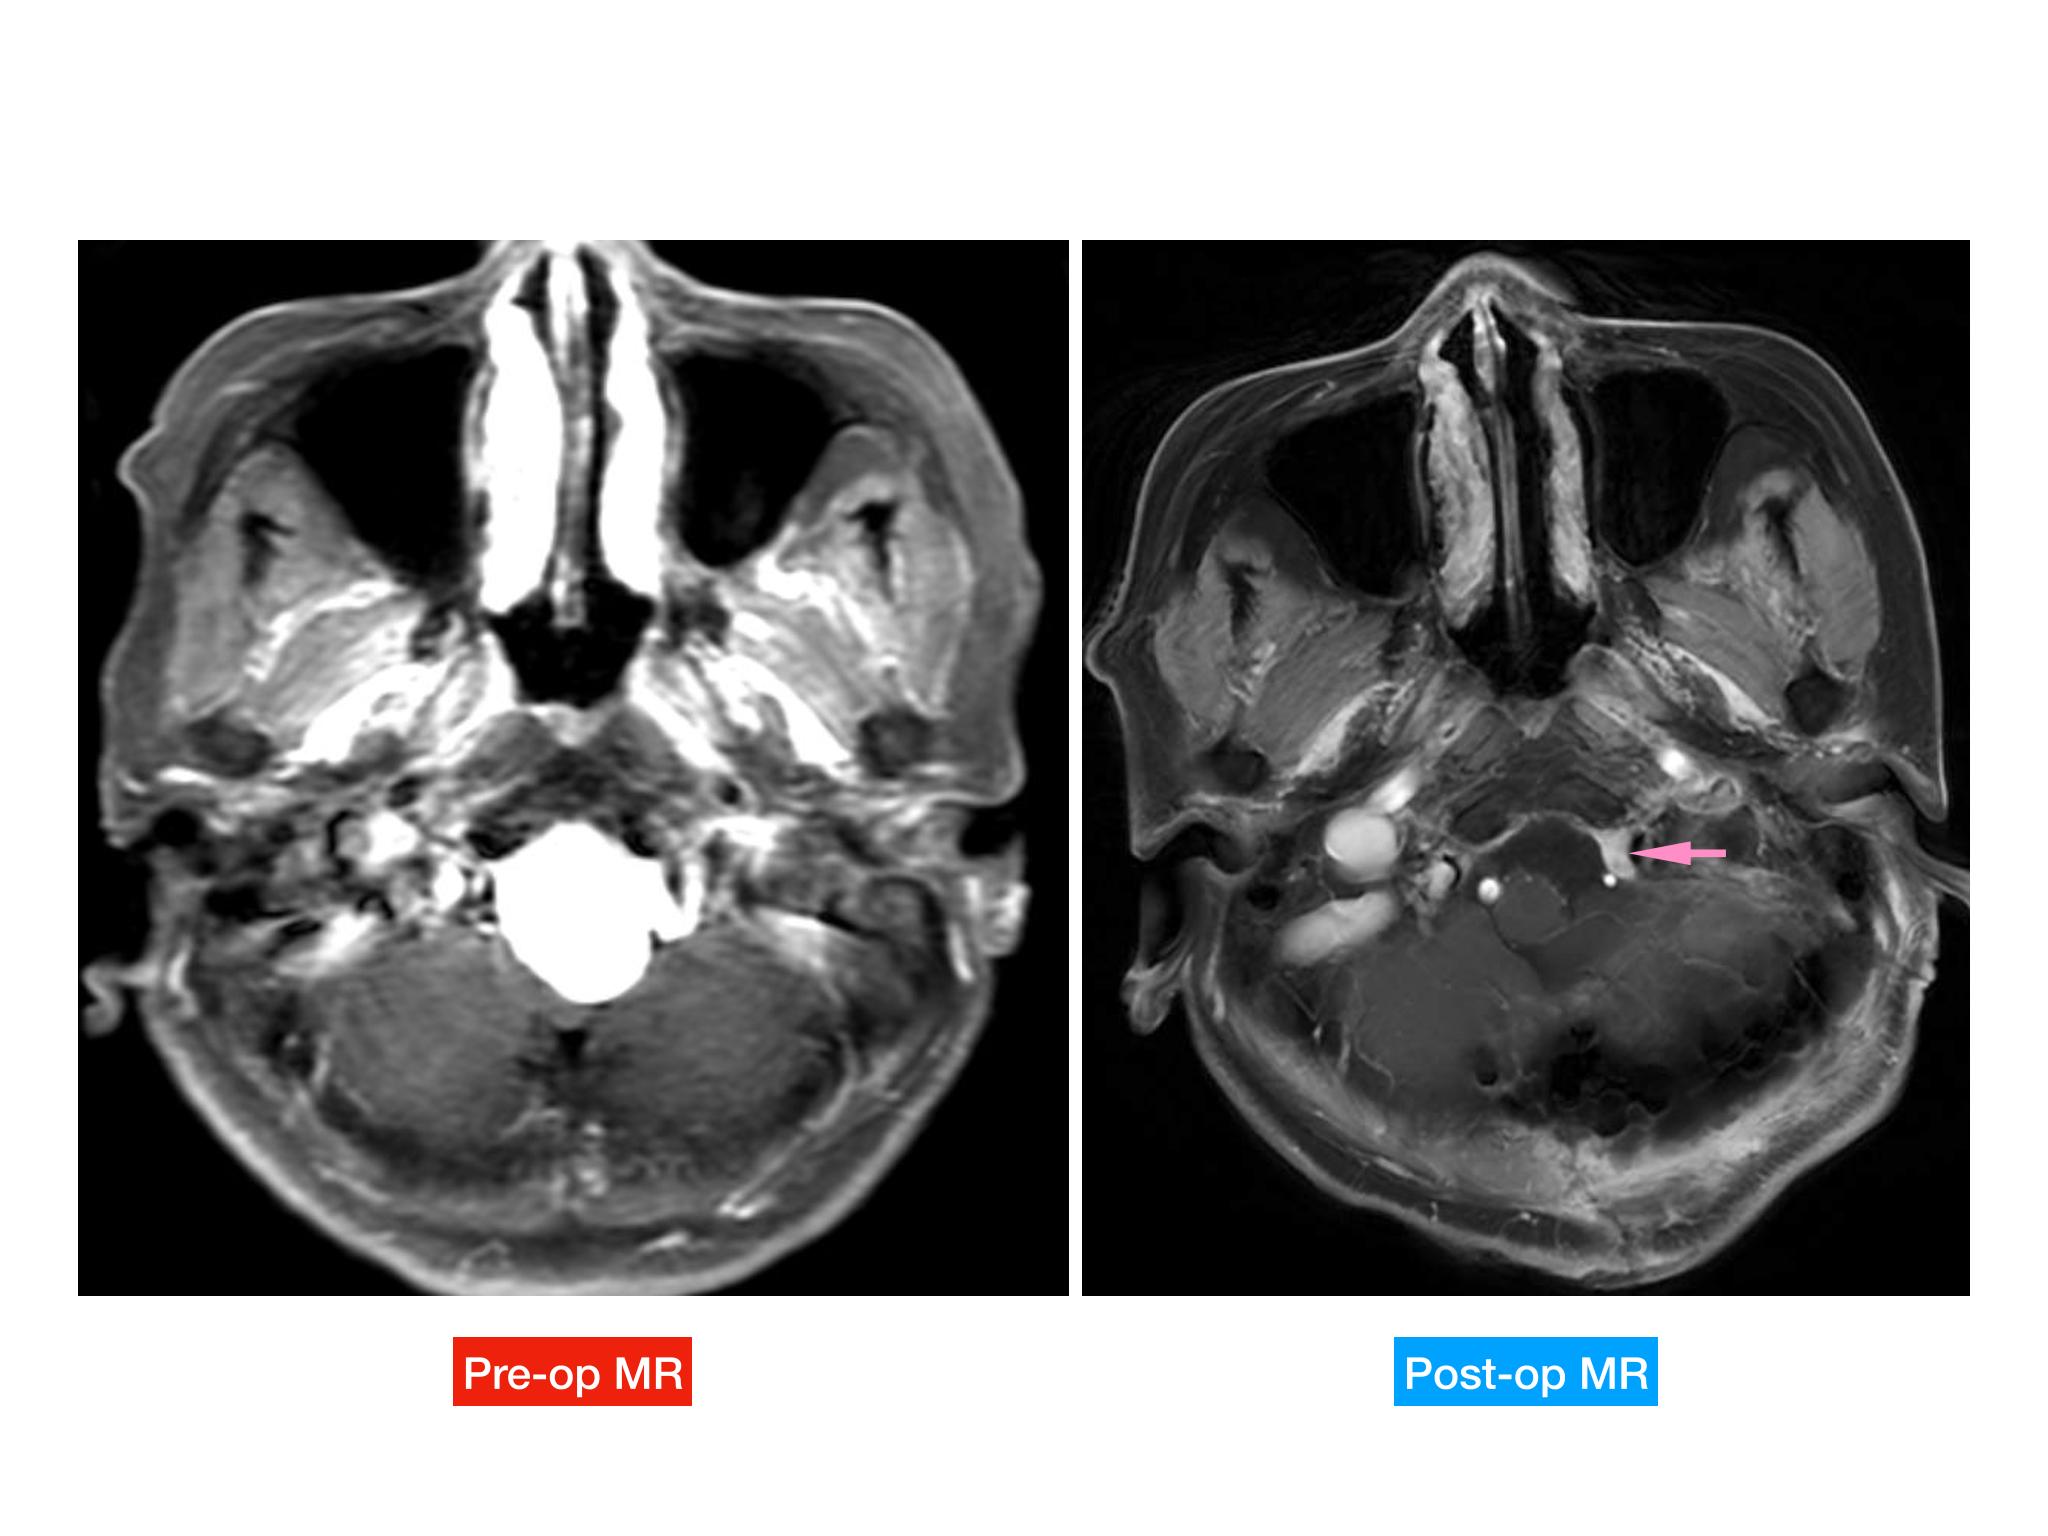

汇报一例后颅底肿瘤手术。为枕骨大孔巨大腹侧型脑膜瘤,该患者高龄,同时合并肺Ca,术前2周急性加重,枕骨大孔疝前期表现,术前已有延髓压迫及后组颅神经麻痹表现。经详细评估后采用远外侧经髁窝入路,最大化显露,重点保护延髓、后组颅神经,尽可能“零骚扰”。术中肿瘤质地韧,血供一般,与肿瘤上极与后组颅神经黏连紧密,最终99%切除,残留约1%,术后顺利康复出院,无新发症状,为后续进行肺部病变化疗创造有利条件。